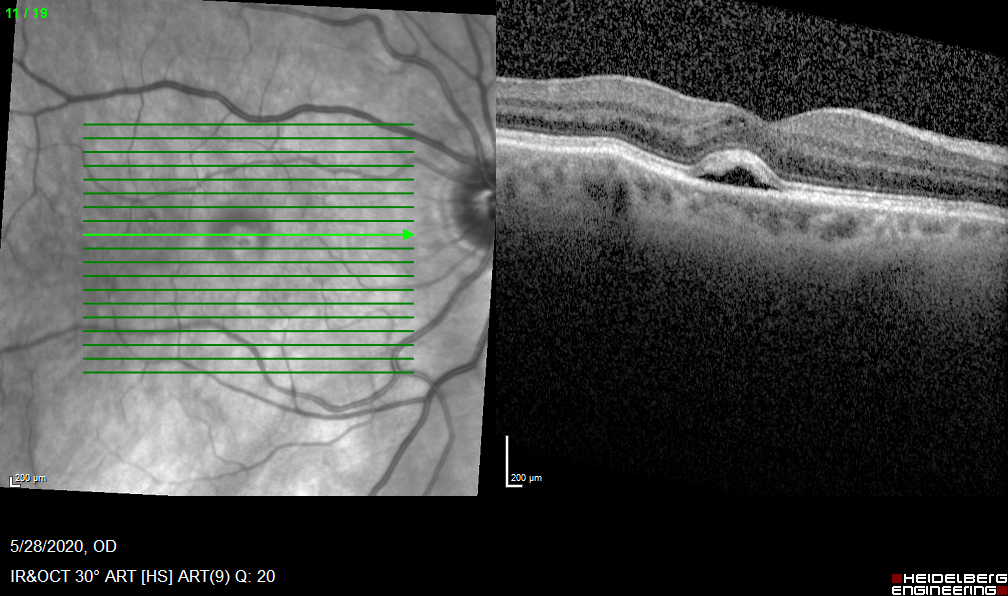

Bilateral Macular holes. When to operate?